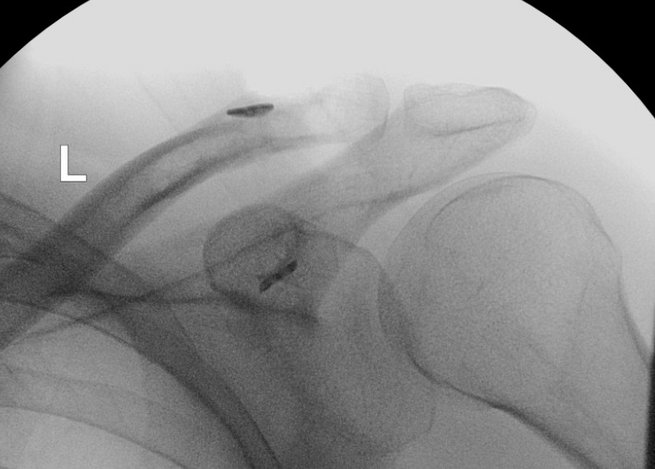

Eine AC-Gelenksprengung ist eine Verletzung des Schultereckgelenks (Akromioklavikulargelenks), meist nach einem Sturz direkt auf die Schulterspitze. Dabei zerreißen – je nach Schweregrad – die Bandverbindungen zwischen Schlüsselbein und Schulterblatt (AC- und/oder CC-Bänder). Typisch sind eine sichtbare Stufe über dem Schultereckgelenk („Klaviertastenphänomen“) und Bewegungsschmerzen bei Armhebung.

Leichte Formen (Rockwood I–II) werden konservativ behandelt, meist mit Ruhigstellung und frühzeitiger Mobilisierung.

Höhere Grade (III–V, selten VI) erfordern häufig eine operative Stabilisierung, insbesondere bei jungen, aktiven oder sportlich ambitionierten Patientinnen und Patienten.

• Faden-Button-Systeme (z. B. TightRope, Dog Bone, Twin Tail):

Minimalinvasiv arthroskopisch oder offen durchgeführt. Zwei kleine Bohrkanäle verbinden das Schlüsselbein mit dem Rabenschnabelfortsatz (Coracoid).

Vorteile: keine Metallentfernung nötig, geringere Weichteilirritation, schnellere Rehabilitation.